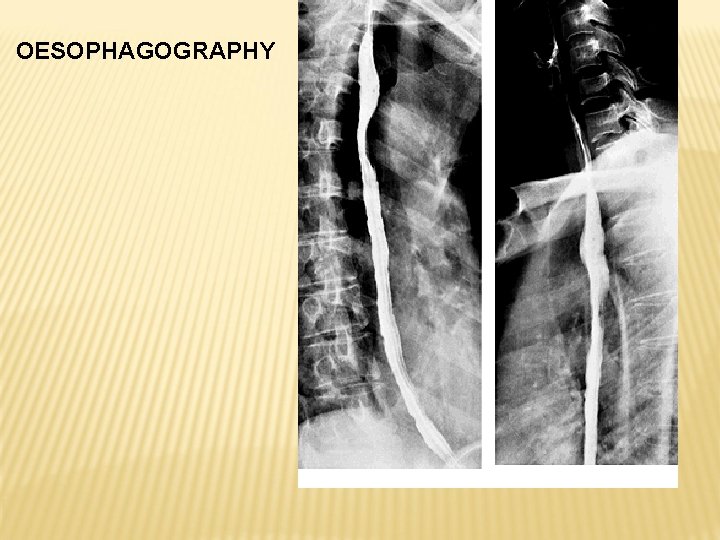

OESOPHAGUS

PARS CERVICALIS PARS THORACICA - PARS RETROTRACHEALIS - PARS RETROPERICARDIACA

PARS ABDOMINALIS

GASTROOESOPHAGEAL JUNCTION Musculature – striated, smooth

OESOPHAGOGRAPHY